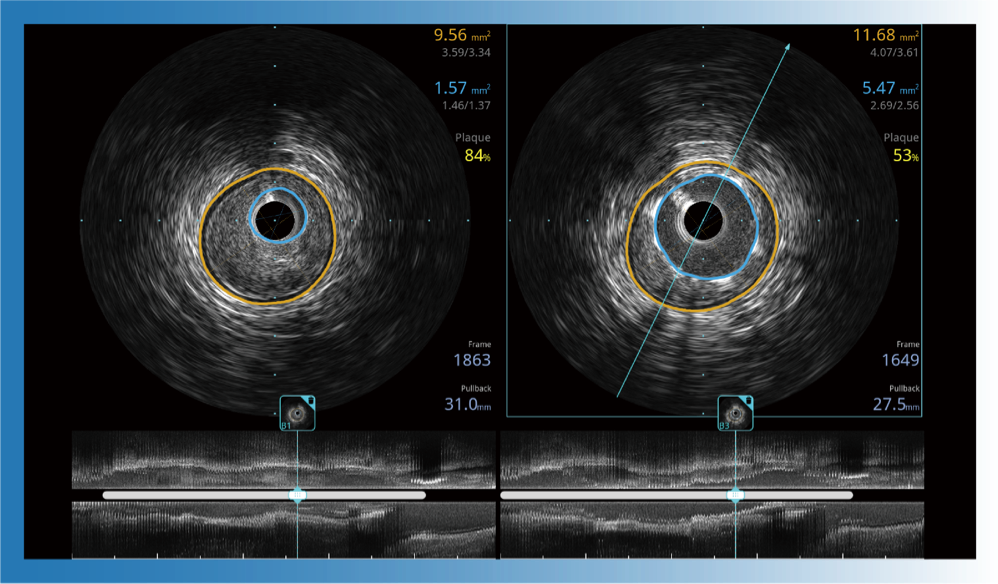

治療前后兩次測(cè)量錄像對(duì)比

簡(jiǎn)化療效評(píng)估

一鍵智能描跡,自動(dòng)測(cè)量斑塊負(fù)荷、面積狹窄率等指標(biāo),準(zhǔn)確率高于90%